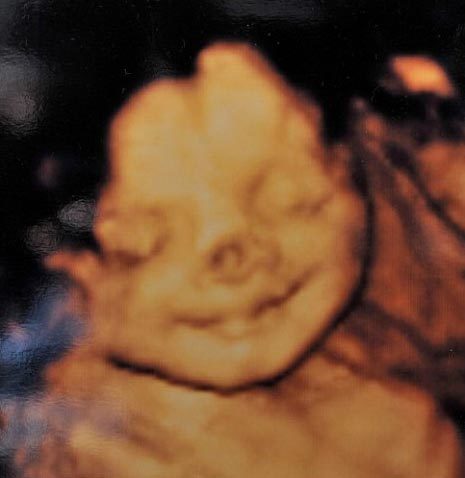

| Hình ảnh siêu âm thai ở tuần 32 cho thấy bé Connie có một vết sẫm màu rất rõ trên mũi. Ảnh: SWNS. |

Theo tờ Daily Mail, các bác sĩ đã phát hiện ra một vết sẫm màu trên mũi của bé Connie Lloyd khi siêu âm thai ở tuần 26. Tuy nhiên, khi cất tiếng khóc chào đời vào tháng 9/2008, cô bé trông có vẻ hoàn toàn khỏe mạnh.